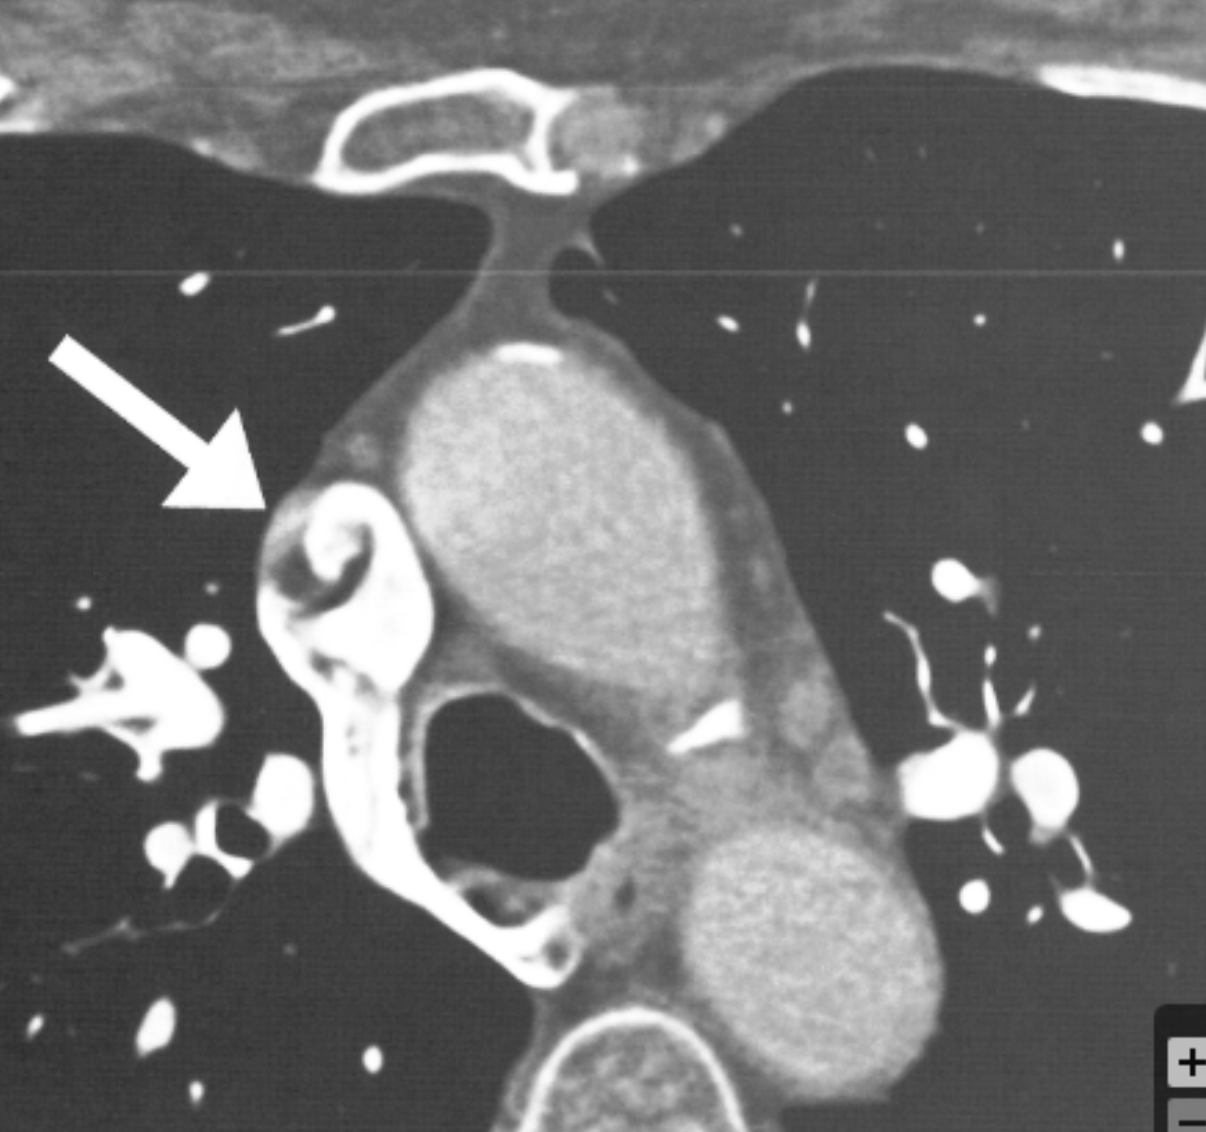

What is the arrow pointing at?

RV pacemaker leads - metal artifacts